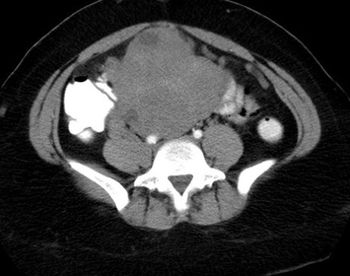

A 17-year-old male patient, no past medical history, presented with two-month history of left groin swelling with gradual increase in size and now pain.